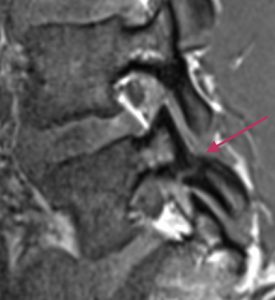

Lannerangan magneettikuva 1

Lannerangan sivuprofiili (sagittaalikuva).